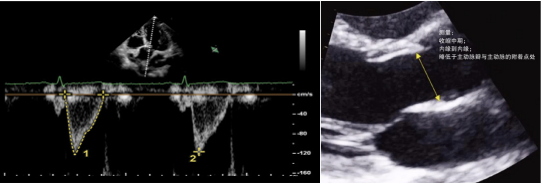

(4)肺血管阻力(PVR):根据三尖瓣反流峰值流速(TRV)和右室流出道速度-时间积分比值(VTIRVOT),可以帮助测量肺血管阻力(PVR)。其计算公式为:

PVR=TRV/VTI×10+0.16

(5)心输出量(CO):一般在心尖五腔心切面和胸骨旁长轴切面进行测定图35。在心尖五腔心切面,使用PW模式获取主动脉血流频谱,描记测量其流速-时间积分(VTI)。在胸骨旁长轴切面,测量主动脉瓣环直径或者左室流出道直径D。则在主动脉无明显反流的情况下,我们可以计算得患者的心排量如下:

CO=π×(D/2)2×VTI×HR

图片

图35. 主动脉瓣VTI的测量和主动脉瓣瓣环内径的测量